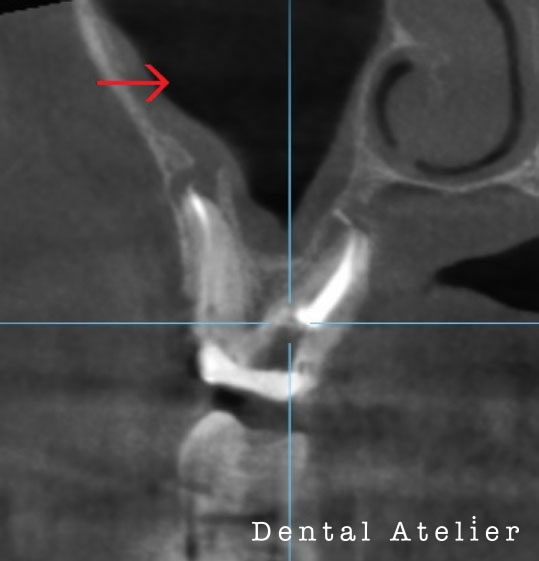

MTAセメントにて根管充填を行い、5か月後のCT写真です。

初診時

5か月後

初診時、矢印の先にあった黒い影(膿の袋)が5か月後には無くなり、溶けた骨が再生してきています。

完全に骨化するには半年以上かかる見込みです。

40代男性 右上7番目

若い頃に神経を取る治療をしたが、10年前に膿が溜まって歯ぐきが腫れてきたので、根管の再治療を行うも、現在まで違和感が消えないと当院を来院しました。

階段を降りる時に響くかんじ、アルコールを飲むと違和感がでるとの事でした。

根の先端から、副鼻腔(蓄膿症になる鼻の空洞)へ感染が起り、矢印の場所が灰色になっています。膿が溜まっています。

根管治療、一か月後

無菌的な処置により、炎症が引いて、矢印の場所に正常な黒い空洞に戻ってきました。歯が原因で鼻の空洞に炎症が起ることがあります。歯性上顎洞炎。